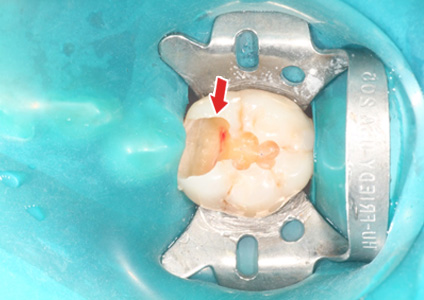

½Å°æÄ¡·á 1.

ÃæÄ¡Ä¡·á Áß¿¡ Ä¡¼ö°¡ ³ëÃâµÈ ¸ð½À - 2